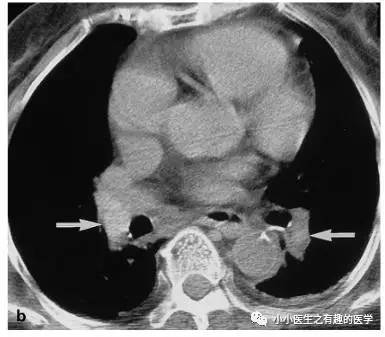

如图,高密度影的那一条。不怕,有增强CT证实。

仔细看,有端倪。增强CT可以核实。

很明显,病人做了CT平扫,我们要仔细阅片,发现可疑,及时增强CT,要不然就漏诊了。